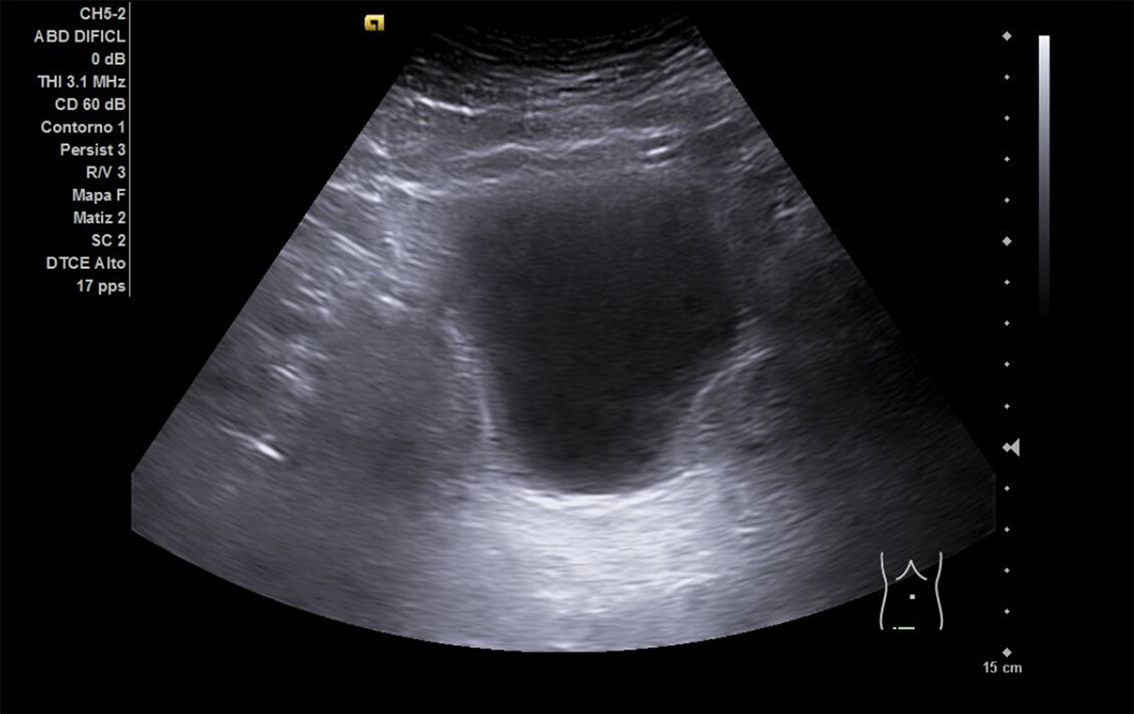

Se realiza ECO POCUS en la que se aprecia riñón derecho de morfología y tamaño normal. Riñón izquierdo con hidronefrosis grado III. A nivel de vejiga, bien replecionada se aprecia masa a nivel de pared izquierda adyacente a unión ureterovesical de 1.8 x 2,7 cm Ausencia de jet izquierdo.